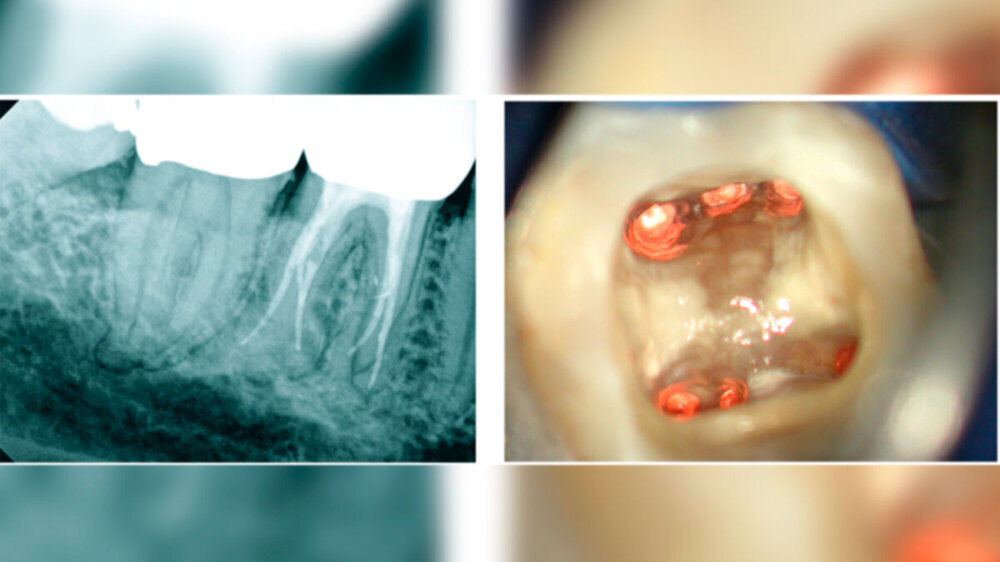

Die AutorInnen berichten, dass eine disto-linguale Wurzel bereits in der Literatur erwähnt wurde („Radix entomolaris“). Sie beschreiben die DLR als kurz, konisch und in bukko-linguale Richtung gekrümmt, wobei letzteres Merkmal die endodontische Aufbereitung erschwere.

Die Prävalenz scheint in unterschiedlichen Bevölkerungsgruppen stark zu variieren: „Studien an Kaukasiern haben ergeben, dass die Häufigkeit nur 1,7 bis 4,2 Prozent beträgt, während Mongolen eine Häufigkeit von 24,5 bis 27,0 Prozent aufweisen.“ Die vorliegenden Studienergebnisse sehen die AutorInnen als Bestätigung dafür, dass die DLR häufiger in ostasiatischen Bevölkerungsgruppen vorkommt. Sie schlagen deshalb vor, dies bei jenen eher als Normvariante denn als Anomalie zu betrachten.